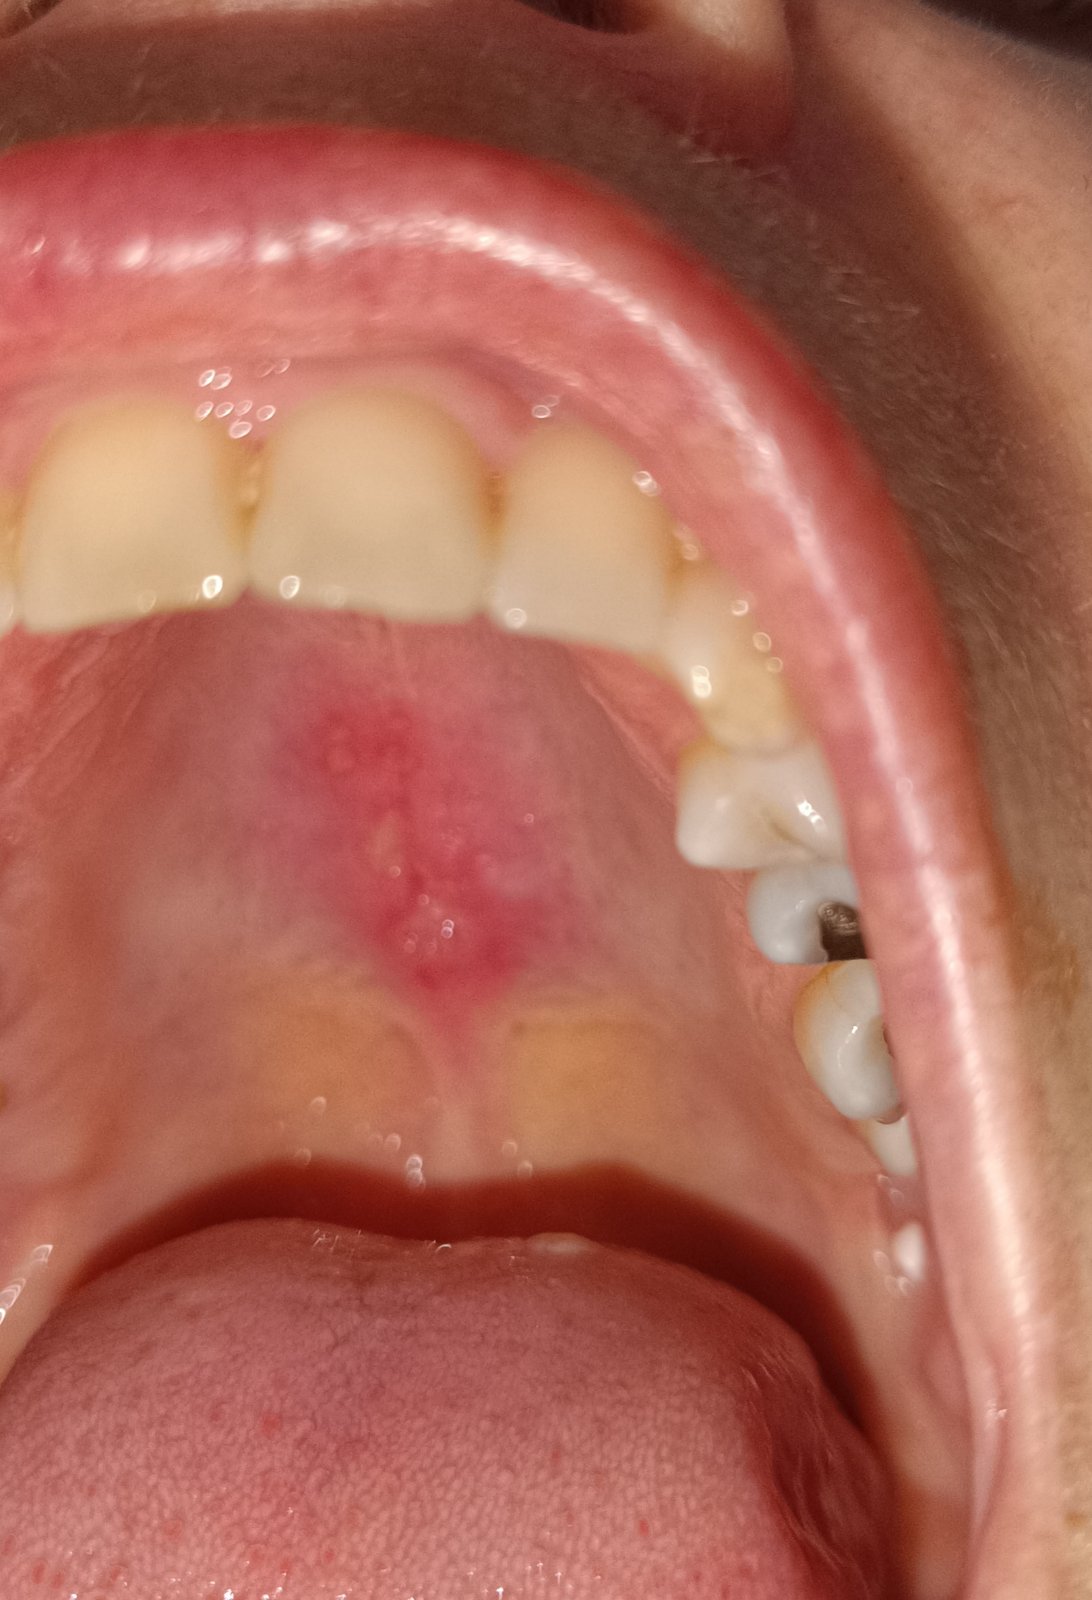

Čo pomôže na takéto bolestivé podnebie? Nepoškodila som si to nijako mechanicky, skôr si myslím či to nieje po uzivani atb, mala som dvoje ATB počas dvoch týždňov, čo by mi na to pomohlo? Na ORL pôjdem v utorok

Vitamin B, riboflavin, nejaký gel z lekárne. To vyzerá na afty.

Zried sodu bikarbonu lyzicku s 1dcl vody